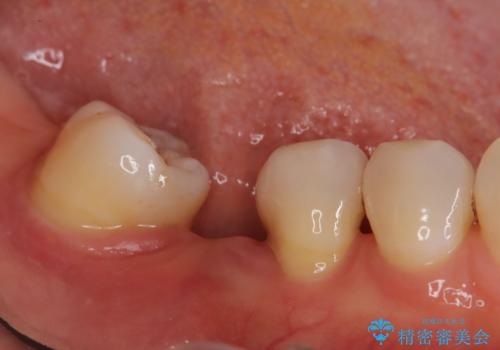

- 歯がぐらぐらしてきて怖いとのことで、当院に来院された患者様です。

右下小臼歯は歯周病で大きな骨欠損を認めていました。

できる限り歯が保存できるように治療したいとのことでエムドゲインを用いた再生治療を行っています。

欠損歯に関しては、奥歯をアップライトさせてインプラント埋入予定です。